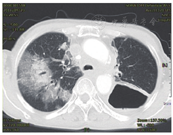

病史:患者2012年9月出现进流质饮食哽咽感,胃镜检查示:距门齿27~30cm肿物。活检示:鳞癌细胞。2012年9月24日在北京某医院行食管大部分切除、食管胃弓上吻合术,术后病理:食管溃疡型中分化鳞状细胞癌。术后分期不详,未行辅助治疗。2014年12月再次出现进食哽噎感,未诊疗。2015年3月出现声音嘶哑,就诊山东省某医院,超声检查示:双侧锁骨上、双侧腋窝淋巴结肿大。胸部CT示:食管癌纵隔、腹腔内淋巴结转移;胃镜吻合口活检:鳞状细胞癌。2015年3月30日给予吻合口、纵隔及腹膜后淋巴结IMRT 54Gy/30次,多西他赛50mg d1、8单药同步化疗1周期,序贯多西他塞60mg d1,40mg d8+顺铂20mg d1~5+西妥昔单抗500mg d1方案治疗2周期。治疗期间骨髓抑制Ⅲ度,复查CT疗效评价SD。2015年7月17日行第3周期多西他塞100mg d1,顺铂20mg d1~5方案化疗,2015年8月12日第4周期改为多西他赛100mg d1+卡铂500mg d2方案化疗1周期,治疗期间骨髓抑制Ⅲ度,胃肠道反应Ⅲ度。于2015年9月8日、2015年10月5日行多西他赛+卡铂方案2周期化疗,化疗后患者无明显不适。2015年11月下旬又出现进食阻挡感,胸部CT检查提示纵隔淋巴结转移治疗后较前进展,双侧锁骨上淋巴结转移,给予纵隔及锁骨上淋巴结精确放疗(病例22图1),1.2Gy,2次/天,共42次,92% PTV 50.4Gy,放疗后予长春瑞滨40mg d1~3+替吉奥40mg 2次/天d1~14方案化疗1周期,骨髓抑制Ⅲ度。2016年5月19日门诊复查示右肺转移(病例22图2)。既往高血压病10余年,食管癌术后血压复常。脑梗死8年余,无明显后遗症。